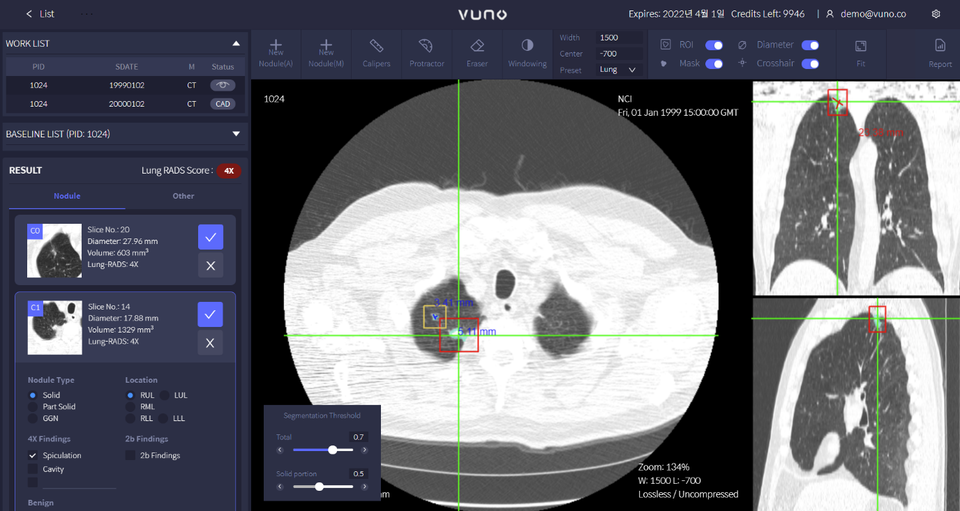

뷰노메드 흉부 CT AI는 AI를 기반으로 흉부 CT 영상에서 탐지된 폐결절의 종류와 위치, 지름과 부피 등의 특징 정보를 제공하는 솔루션이다. 초해상도(Super Resolution) 알고리즘을 적용해 기술적 완성도를 높인 것이 특징이다.

뷰노의 이번 기술은 이런 노력을 줄일 수 있는 기반이 된다. 의료진은 흉부 CT 영상 두께를 자유롭게 전환할 수 있게 됐으며 이를 바탕으로 슬라이스 두께 차이에서 발생할 수 있는 분석 결과의 오류를 줄여 폐결절 탐지 정확도를 높일 수 있을 전망이다.